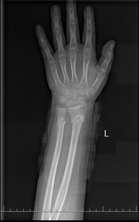

骨折愈合正位

整复后X线片提示接近解剖复位,40天达到临床愈合,最后随访时患肢外形及功能均完全正常。

9月11日复查查体时见患处无压痛及叩击痛,X线片见骨折线模糊,有足量骨痂形成,符合临床愈合标准,予拆除小夹板,患者左前臂无明显肌肉萎缩,左腕关节无僵硬,未出现筋膜室综合征和神经损伤等并发症。